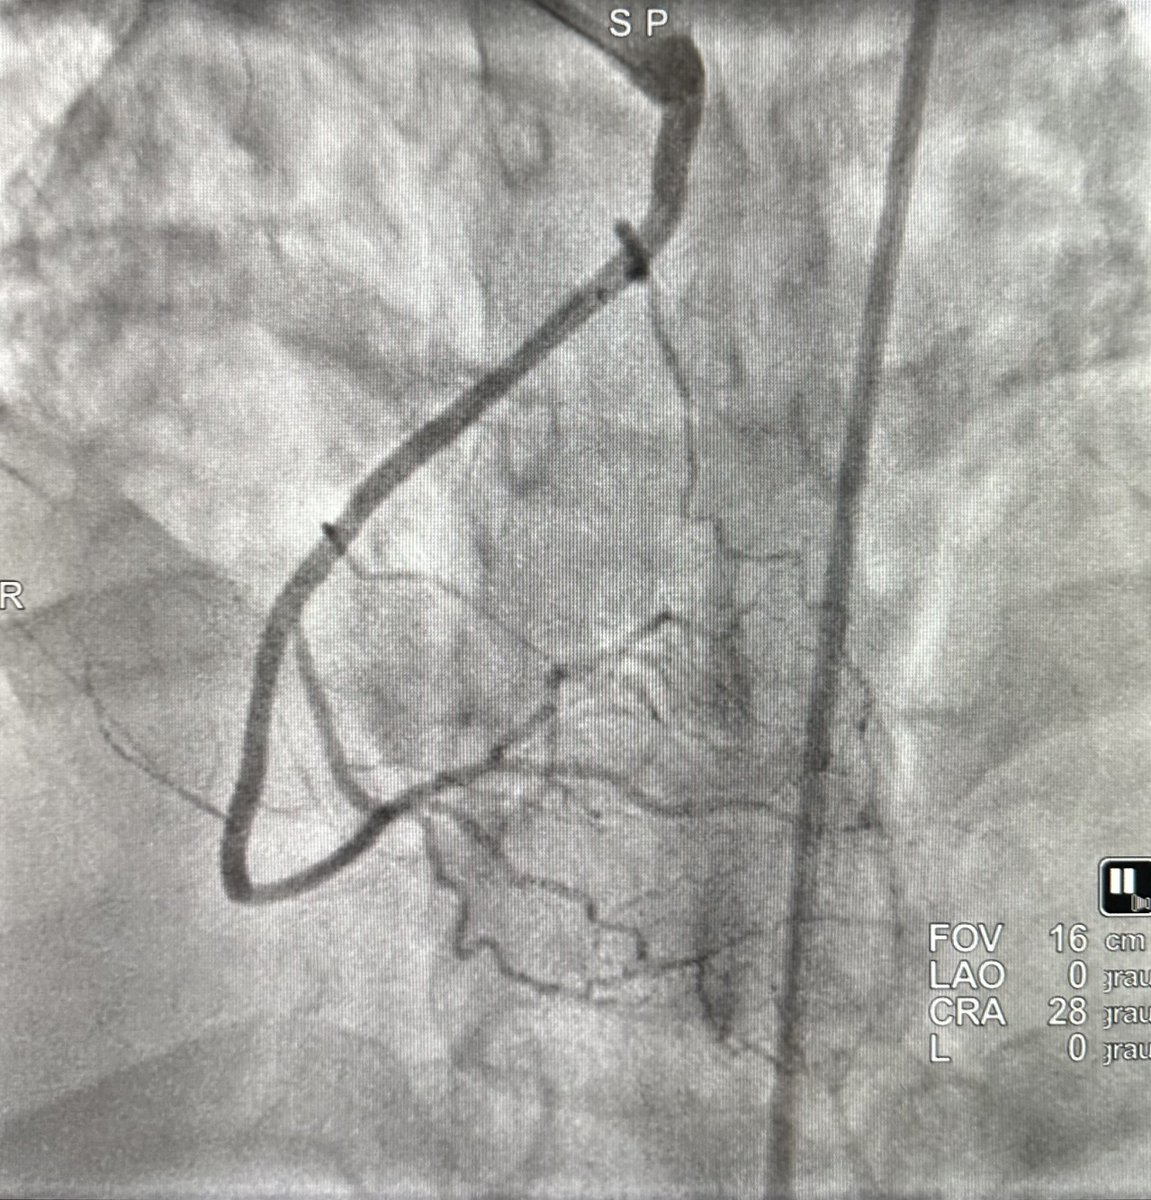

Antegrade CTO Intervention of RCA. “Simple approach”. Single access / Single CTO wire / Single MC. Blunt/Calcium/Angulation/Antegrade filling from ipsilateral collaterals. #CTO101 #ICFIT

evandrofilhobr's tweet image. Antegrade CTO Intervention of RCA. “Simple approach”.

Single access / Single CTO wire / Single MC.

Blunt/Calcium/Angulation/Antegrade filling from ipsilateral collaterals. #CTO101 #ICFIT